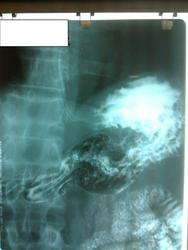

Пациент, 60 лет. На ФГДС: В антральном отделе отмечается некоторая ригидность на малой кривизне, рядом с привратником.

Не вижу изменений в антральном отделе, но обращает внимание некоторая ригидность задне-медиальной стенки субкардиально.

Обратила внимание на уплощение контура на малой кривизне препилорического отдела. Но только на одном снимке, на остальных - без особенностей. Вряд ли стоит придавать этому значение. Вы видели моторику - Вам судить